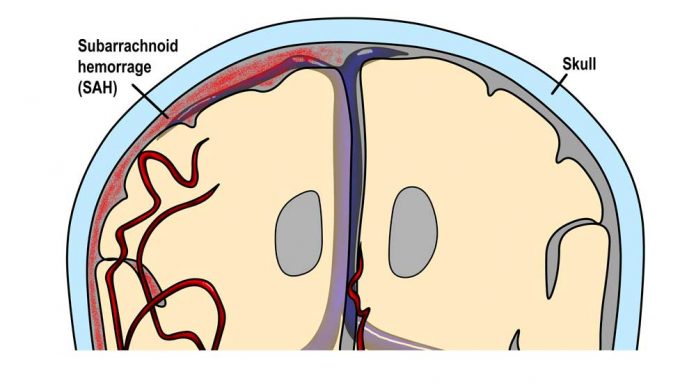

Χρήσιμες πληροφορίες για την υπαραχνοειδή αιμορραγία

Υπαραχνοειδής αιμορραγία καλείται η εξαγγείωση αίματος στον υπαραχνοειδή χώρο, ιδιαίτερα της μεσοσκελιαίας δεξαμενής και εντός των διόδων, όπου ρέει το εγκεφαλονωτιαίο υγρό.